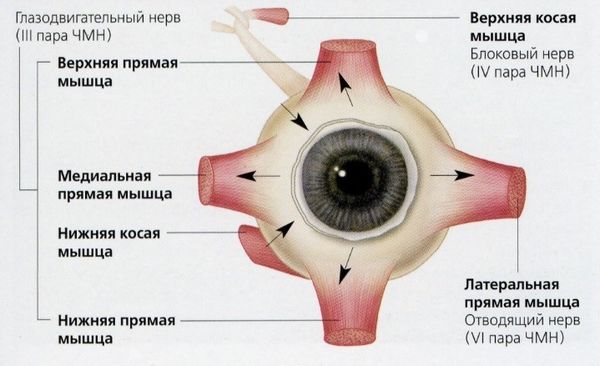

В норме движения глаз согласованы, их обеспечивают шесть глазодвигательных мышц, которыми управляют несколько пар черепных нервов. Однако при поражении нервных центров в головном мозге или самих нервов сигнал к мышцам глаз не передаётся, движение глаз нарушается и развивается бинокулярная диплопия. Так происходит и при некоторых инфекционных заболеваниях (ботулизме, столбняке и болезни Лайма).

Глазодвигательные мышцы

Такие заболевания, как миастения, сопровождаются быстрой утомляемостью мышц, поэтому диплопия проявляется ближе к вечеру или после нагрузки. Это может стать ключевым признаком для постановки диагноза [4][5].

Двоение при эндокринной офтальмопатии возникает из-за воспаления и отёка глазодвигательных мышц, что ограничивает подвижность и смещает глазное яблоко.

Патогенез диплопии при травмах и переломах костей черепа тоже связан со смещением. Например, при переломах нижней стенки орбиты глаз опускается, и появляется выраженное постоянное двоение.